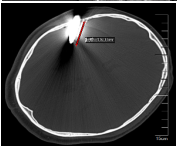

患者头部CT显示钳子穿破颅骨插入脑内近5cm深,周围脑组织有少量出血,一般遇到此种情况,选择的手术方案都是全身麻醉下进行局部切开后拔除钳子,再进行深入的清创止血手术,但这样会对脑部造成二次损伤,颅内损伤面积增大,会导致手术后患者留下严重的后遗症,甚至危及生命。

江峰主任反复阅片并组织科室进行疑难病例术前讨论,认为所幸患者颅内大血管并未伤及,损伤的脑组织位于右侧大脑半球亚功能区,故患者神志仍然清楚,目前无明显神经功能障碍。

手术中拔除的钳子和术后脑部CT